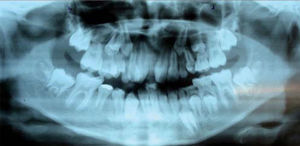

Análisis radiológicoEn las radiografías panorámicas y periapicales las estructuras esqueletales y alveolares son normales a excepción de los ápices de los incisivos centrales y lateral superior derecho que no están bien delimitados.

Un cefalograma fue hecho en oclusión céntrica así como los análisis cefalométricos de Steiner, Jarabak y Ricketts (Cuadro I).

El labio superior, en relación con la línea estética, se encontraba en una posición retruida y el labio inferior en protrusión. El ángulo nasolabial estaba aumentado por el poco soporte labial que ofrecían los centrales superiores (Figuras 1 a 5).